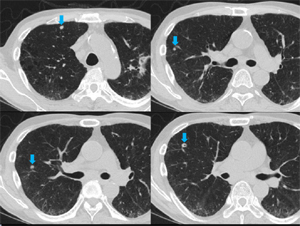

両肺に数少ないが多発結節(小葉との関係は判断困難)の出現、出現速度は速く、増大経過(LVFX抵抗性)

2010.05.27 抗生剤( LVFX )投与開始後 解熱なし

2010.06.2) 初診から5週後

増大したものの一部に空洞形成、左上区の最大のものの空洞内には同心円状・索状構造がみられる